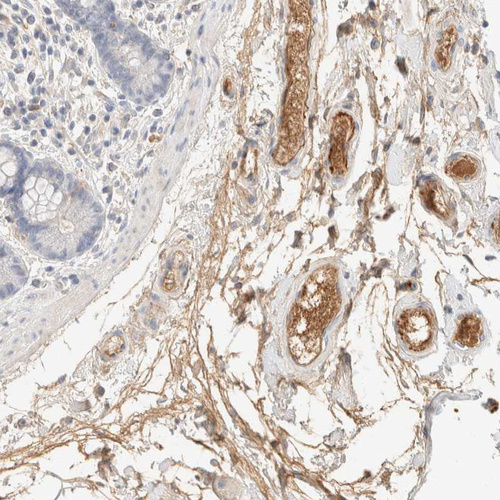

Immunohistochemistry analysis in human liver and cerebral cortex tissues using HPA023694 antibody. Corresponding C8B RNA-seq data are presented for the same tissues.